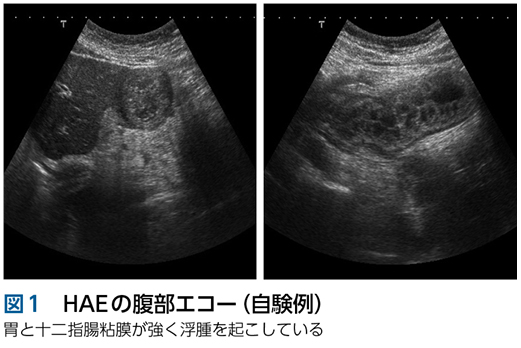

画像診断

腹痛の原因精査の一環で,腹部エコー,腹部CT,消化管内視鏡検査が行われることがあります。特徴は,炎症を伴わない綺麗な粘膜下の浮腫です。これらを認めた場合には,ぜひHAEを想起して下さい(図1〜3)。